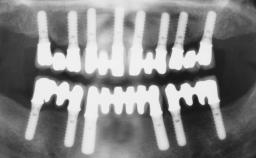

A fully edentulous 65-year-old woman was referred to our clinic for esthetic and functional dental rehabilitation. The patient presented with inadequate complete maxillary and mandibular prostheses, insufficient vertical dimension, and extensive tooth wear. The clinical examination and anamnesis showed no local or systemic contraindications, no signs or symptoms of bruxism, and an absence of smoking habits. The treatment proposed was implant placement in the mandibular interforaminal area and immediate loading with a fixed definitive prosthesis. A removable mucosa-supported complete prosthesis was indicated for the upper jaw, since its bone structure offered satisfactory retention and the financial condition of the patient disfavored a full-mouth implant-supported rehabilitation.

# of Implants 4

Defining Characteristics Fully edentulous lower jaw to be rehabilitated with two or more implants

Modality 3 or 4 interforaminal implants

Defining Characteristics Fully edentulous lower jaw to be rehabilitated with an implant-borne fixed dental prosthesis

Loading Protocol Immediate

Retention Screw-retained, with 4 or more splinted implants Screw-retained, with 4 or more splinted implants